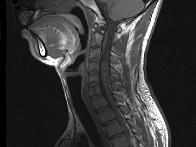

问题 男,24岁,颈部疼痛,并右上肢麻木,以手部明显,请根据所提供图像,选择最可能的诊断()

选项 A.(颈4~5)神经鞘瘤 B.(颈4~5)脊膜瘤 C.(颈4~5)海绵状血管瘤 D.(颈4~5)血管母细胞瘤 E.(颈4~5)胶质瘤

答案 A